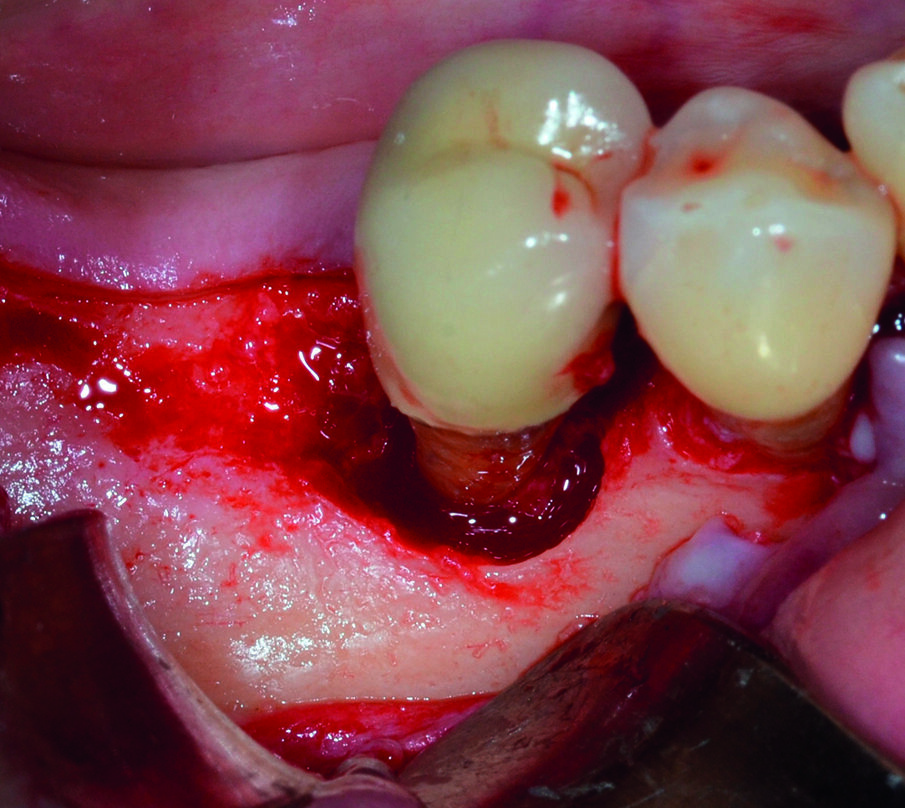

Dopo analgesia locale ottenuta per infiltrazione di Articaina cloridrato 40 mg con epinefrina 1:100.000 viene effettuata l’ incisione di accesso in accordo con il protocollo chirurgico sopra citato (Fig. 4). Al sollevamento del lembo è possibile evidenziare un profondo difetto che coinvolge l’aspetto disto-buccale dell’ elemento 4.5; con una sonda parodontale millimetrata di tipo Williams viene misurata la profondità della componente intraossea (Figg. 5-7). Il debridement della lesione e la decontaminazione della superficie radicolare vengono effettuati mediante una coppia di inserti dedicati montati su dispositivo ad ultrasuoni (ES030LDT ed ES030RDT, Esacrom Srl, Imola, Italia) (Fig. 8).

La particolarità di questi inserti è quella di avere una curvatura orientata verso destra (ES030RDT) e verso sinistra (ES030LDT): in tal modo, risulta molto più agevole operare sul versante buccale o linguale/palatale a seconda dei casi (Figg. 9, 10). Grazie all’effetto combinato della cavitazione ultrasonica e del microstreaming acustico vengono effettuati sia la rimozione del tessuto reattivo che la completa decontaminazione della superficie radicolare (Fig. 11). Al termine del trattamento con ultrasuoni, è possibile valutare l’aspetto intraoperatorio dell’area interessata dal difetto (Fig. 12).